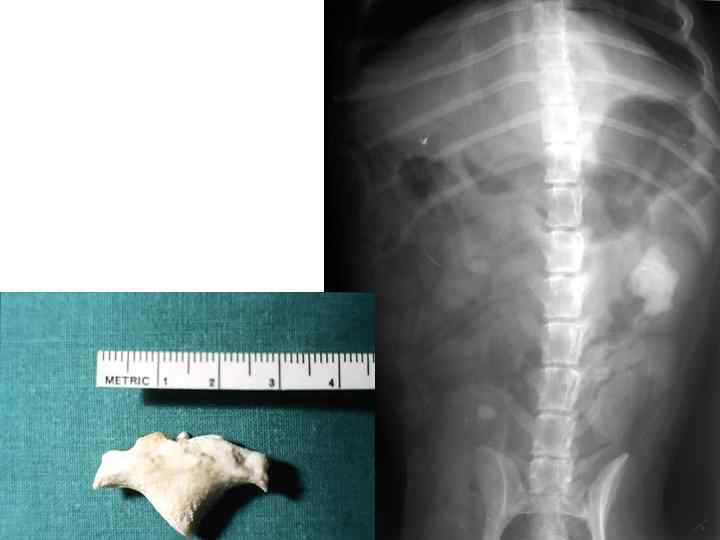

Камень в почке у пекинеса

Камень почечной лоханки